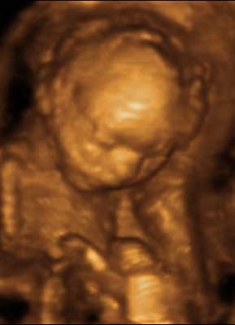

Antes y Después Boxeando Feto de 16 Semanas Feto de 21 Semanas Feto de 26 Semanas

Feto de 16 Semanas